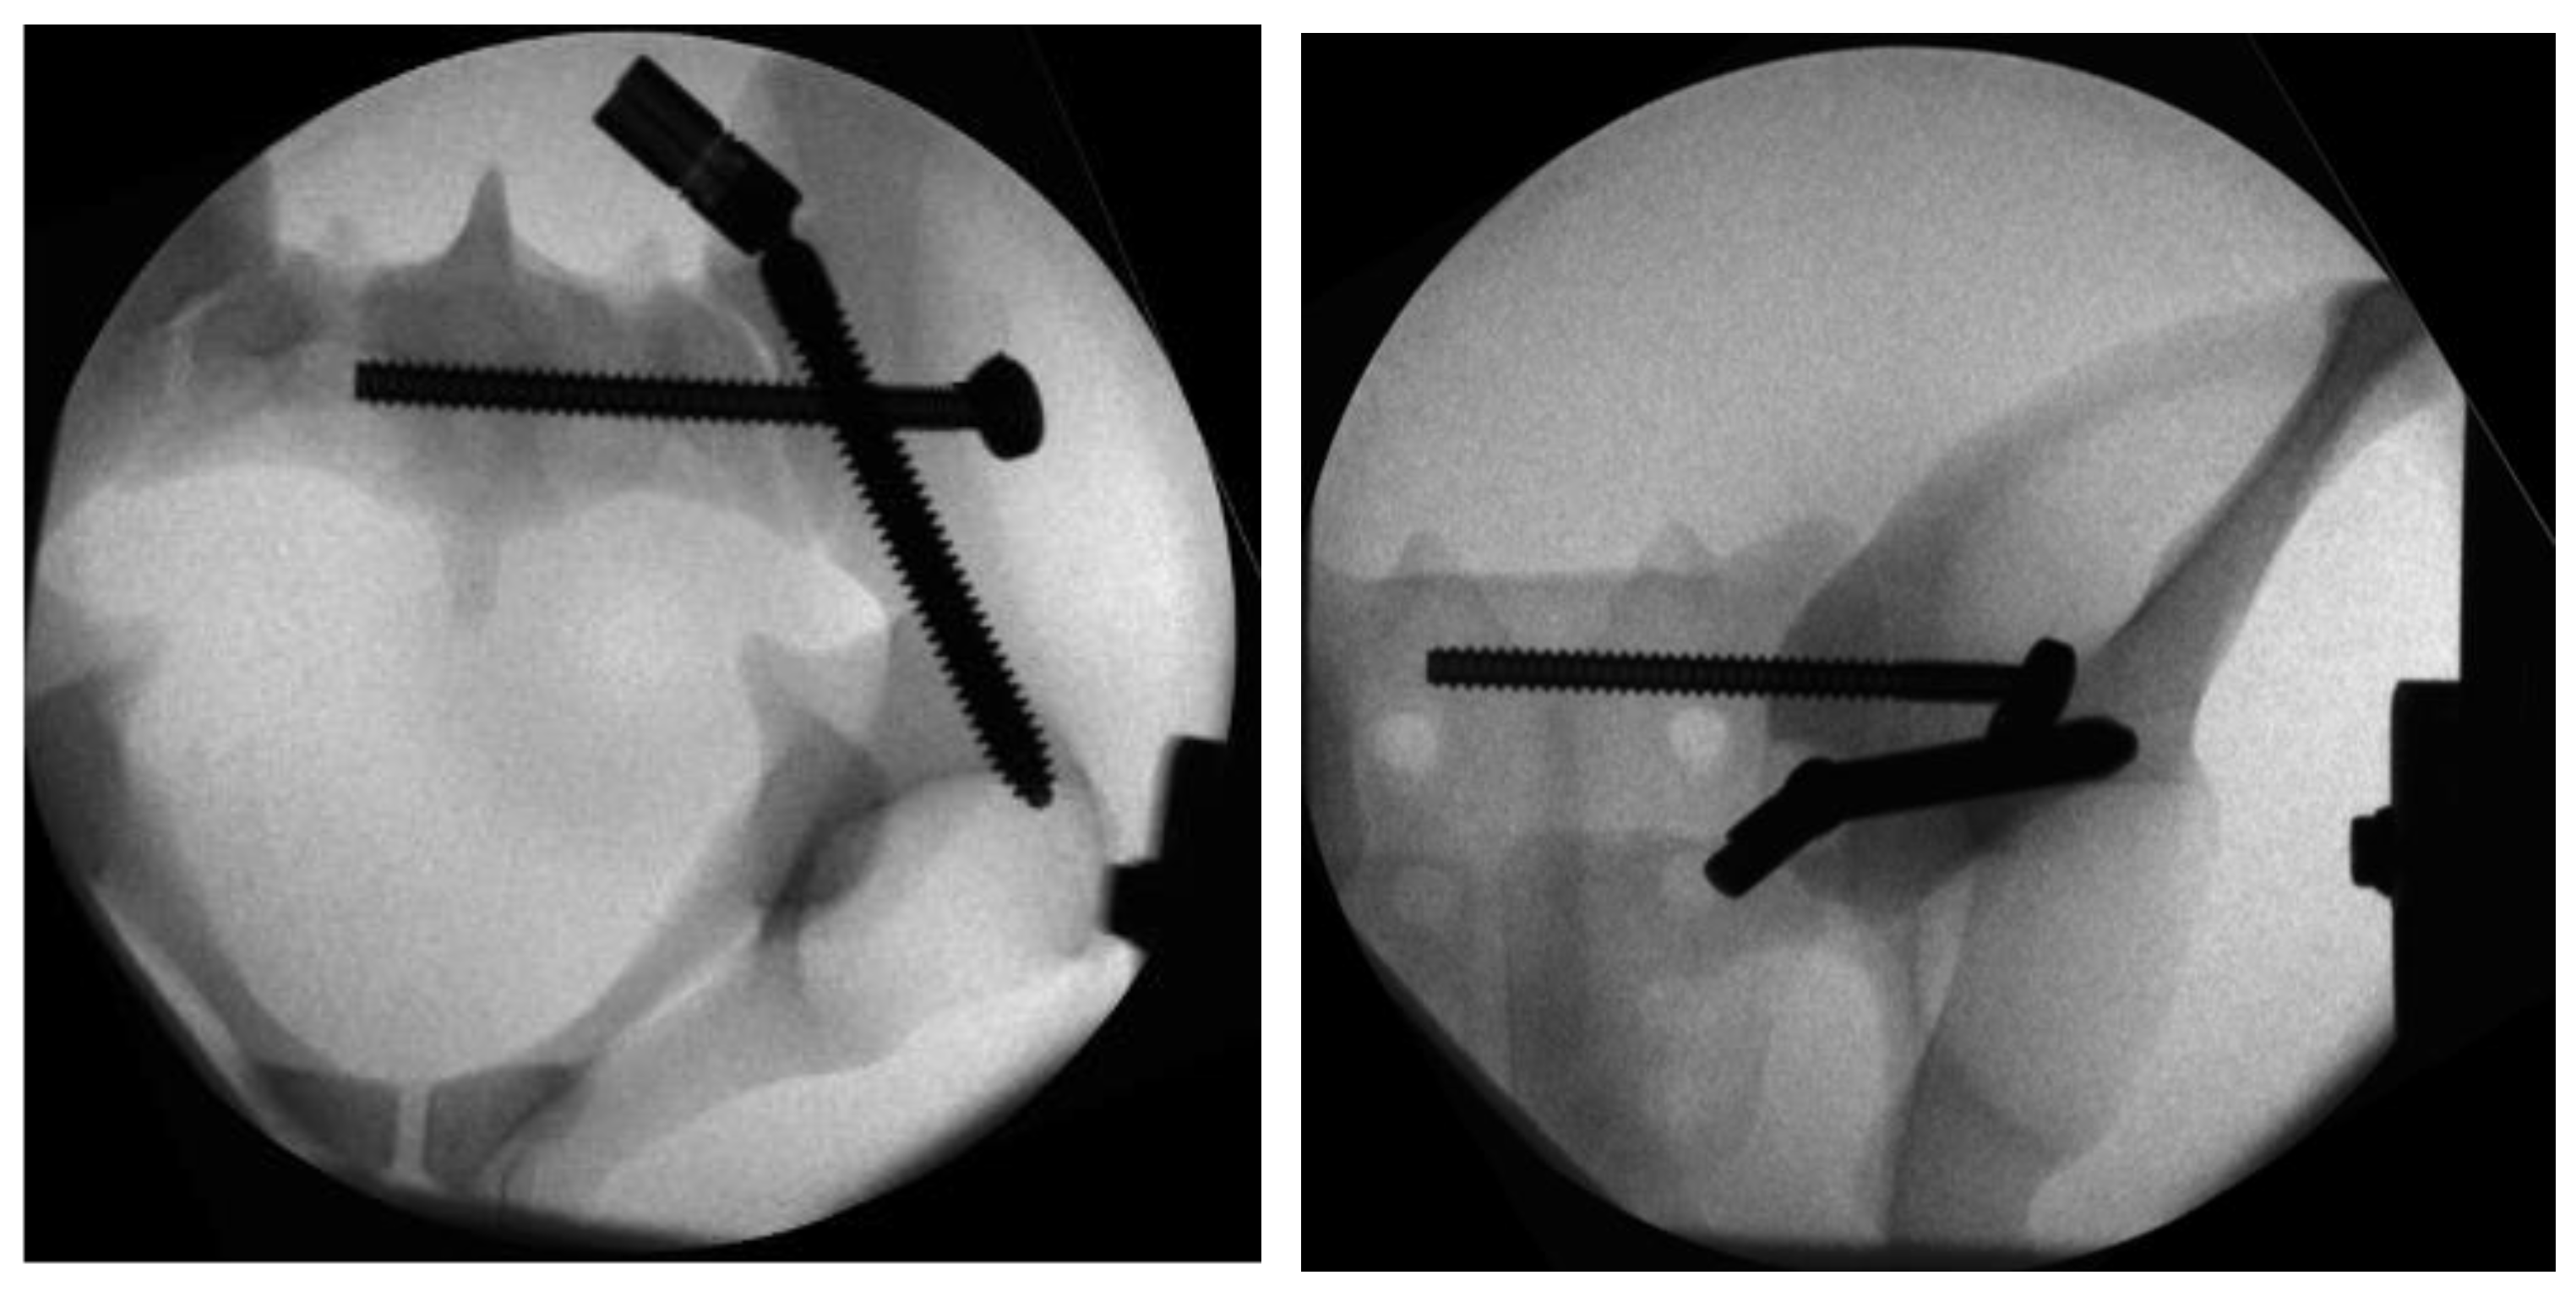

3.4. Catastrophic Construct Failure Mode

Figure 8 and Figure 9 visualize the catastrophic construct failure mode in both groups. The specimens in both groups failed around the implants in addition to failure at the fracture plane. In particular, the hard and brittle outer structure of the artificial bone model resulted in failure in the area of the implant entry points and trajectories.

Figure 8.

Catastrophic failure pattern in the TFS group, particularly the failure in the trajectory of the iliac screw.

Figure 9.

Catastrophic failure pattern in the TF group, particularly the failure in the trajectory of the iliac screw and the sacroiliac screw.